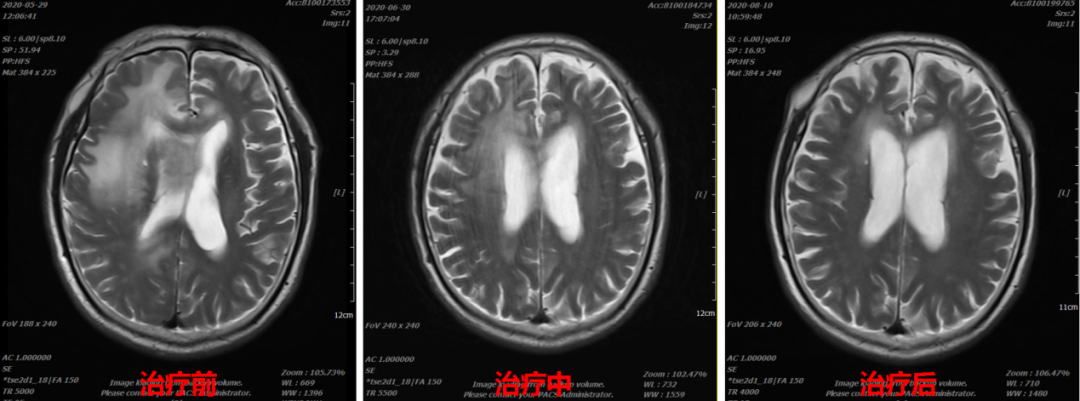

85岁高龄,入院前出现左侧肢体麻木、无力,肢体活动障碍,反应迟缓、小便失禁。头颅核磁提示右侧额叶-胼胝体区胶质母细胞瘤。

图3 碳离子治疗期间的影像对比

图4